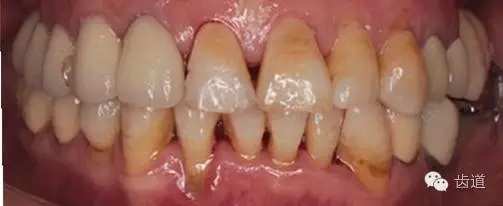

全口衛(wèi)生情況欠佳,可探及齦上及齦下牙結(jié)石,有牙齦探診出血,有牙齦退縮及牙周附著喪失。

1、全口正面觀